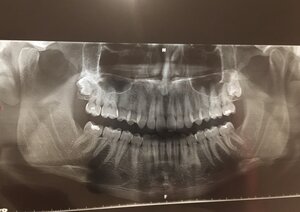

- Cause of Tinnitus

- ETD, TMD, CI